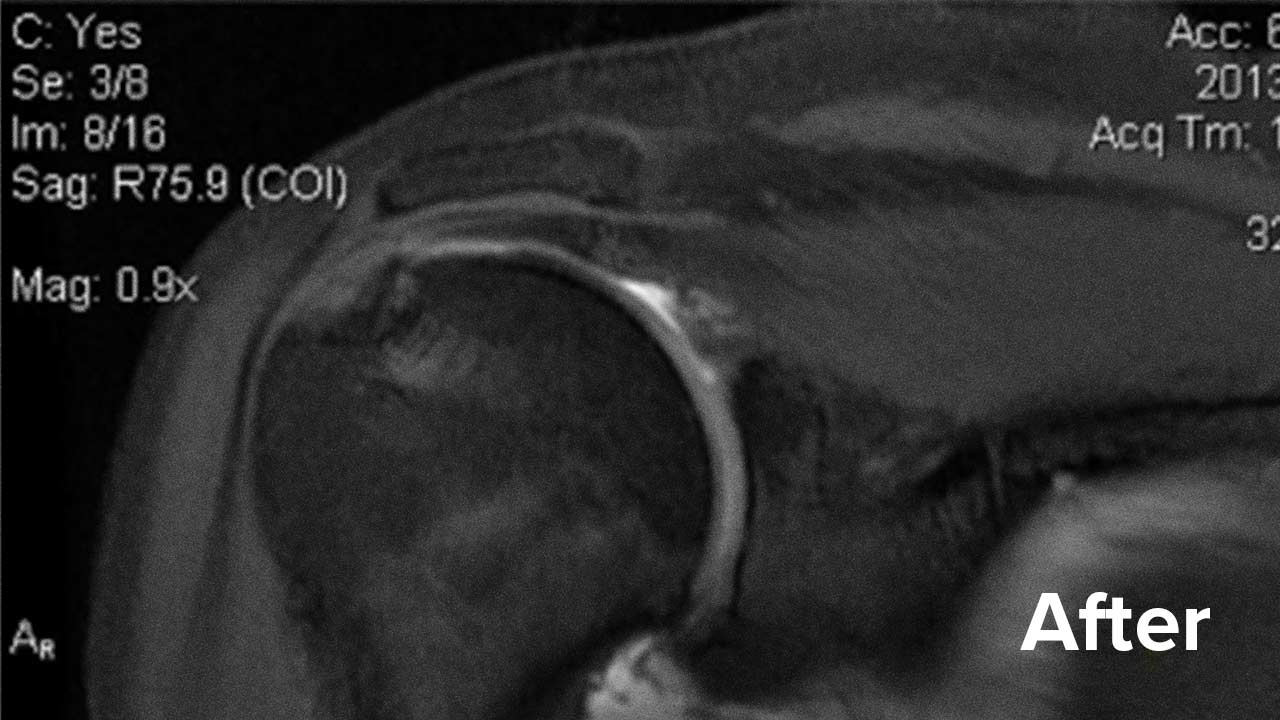

Before and After Shoulder Repair MRI Images

Take a look at the outcomes of two of our patients who chose to have a Regenexx procedure instead of surgery.

Scroll the arrow to the right to see the MRI of the rotator cuff before the treatment and to the left to see the outcome. The BEFORE shows a torn rotator cuff. The arrow points at a gap where the tendon should be. Once treated, the area will look like a dark band going diagonally, as seen on the AFTER.

Patient 1 MRI